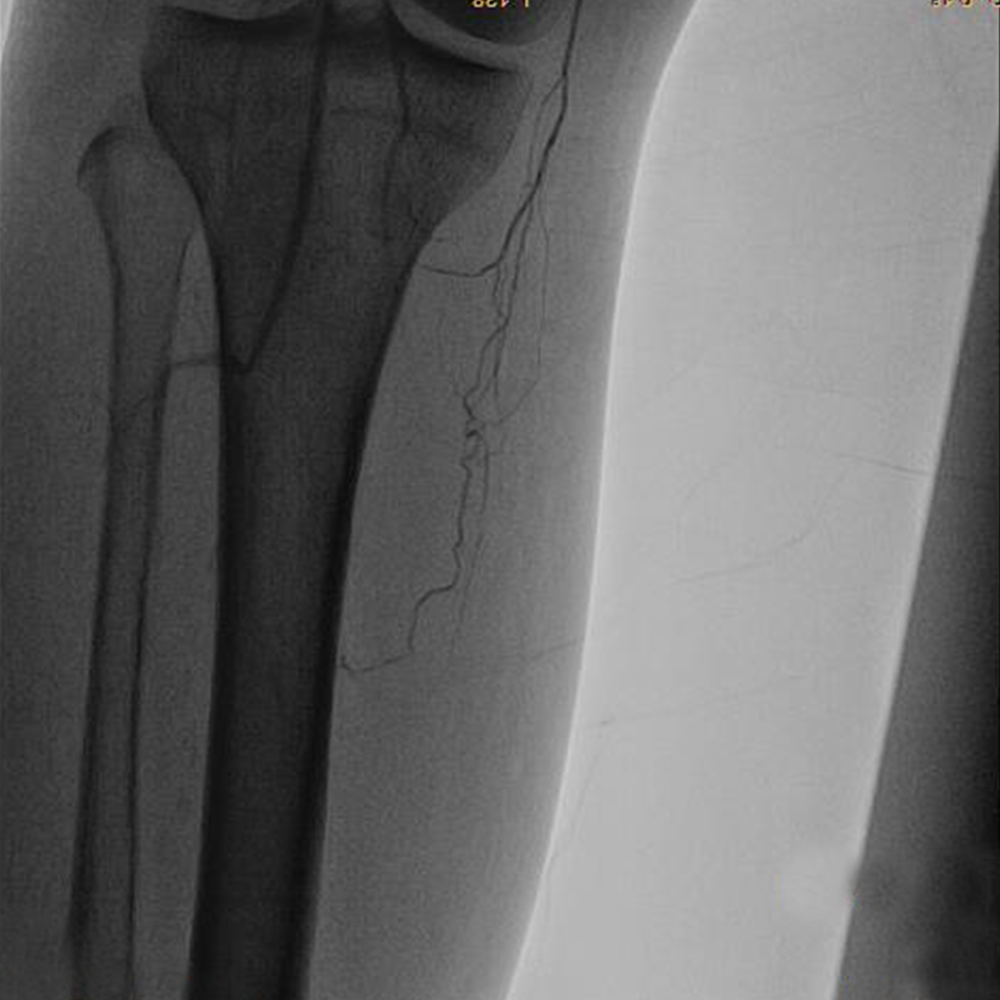

PREOPERATIVE ASSESSMENT AND PREOPERATIVE IMAGING with Duplex scan of lower limb arterial system,CT angiogram and In most patients, standard arteriography is still the “gold standard. If endoluminal therapy is the case, Endoluminal/Endo Vascular treatment at the time of diagnostic arteriography is  performed.

If open bypass is the plan, then  the focus is to visualize potential target arteries and obtain multiple views, as required, to ascertain that no unexpected inflow disease is present that would require treatment before proceeding with Infra inguinal bypass. Although most claudicants require only femoropopliteal bypass, a high proportion of patients with CLI require tibial or pedal bypass. Patients with CLI generally require intervention, since patients with CLI pose a more complex problem because there is a high anticipated amputation rate without lower extremity arterial reconstruction.

Thus, a patent anterior tibial or posterior tibial artery in direct continuity with the foot and pedal arch would be chosen. The preferred conduit for Bypass surgery is Autogenous Vein graft (Saphenous vein)